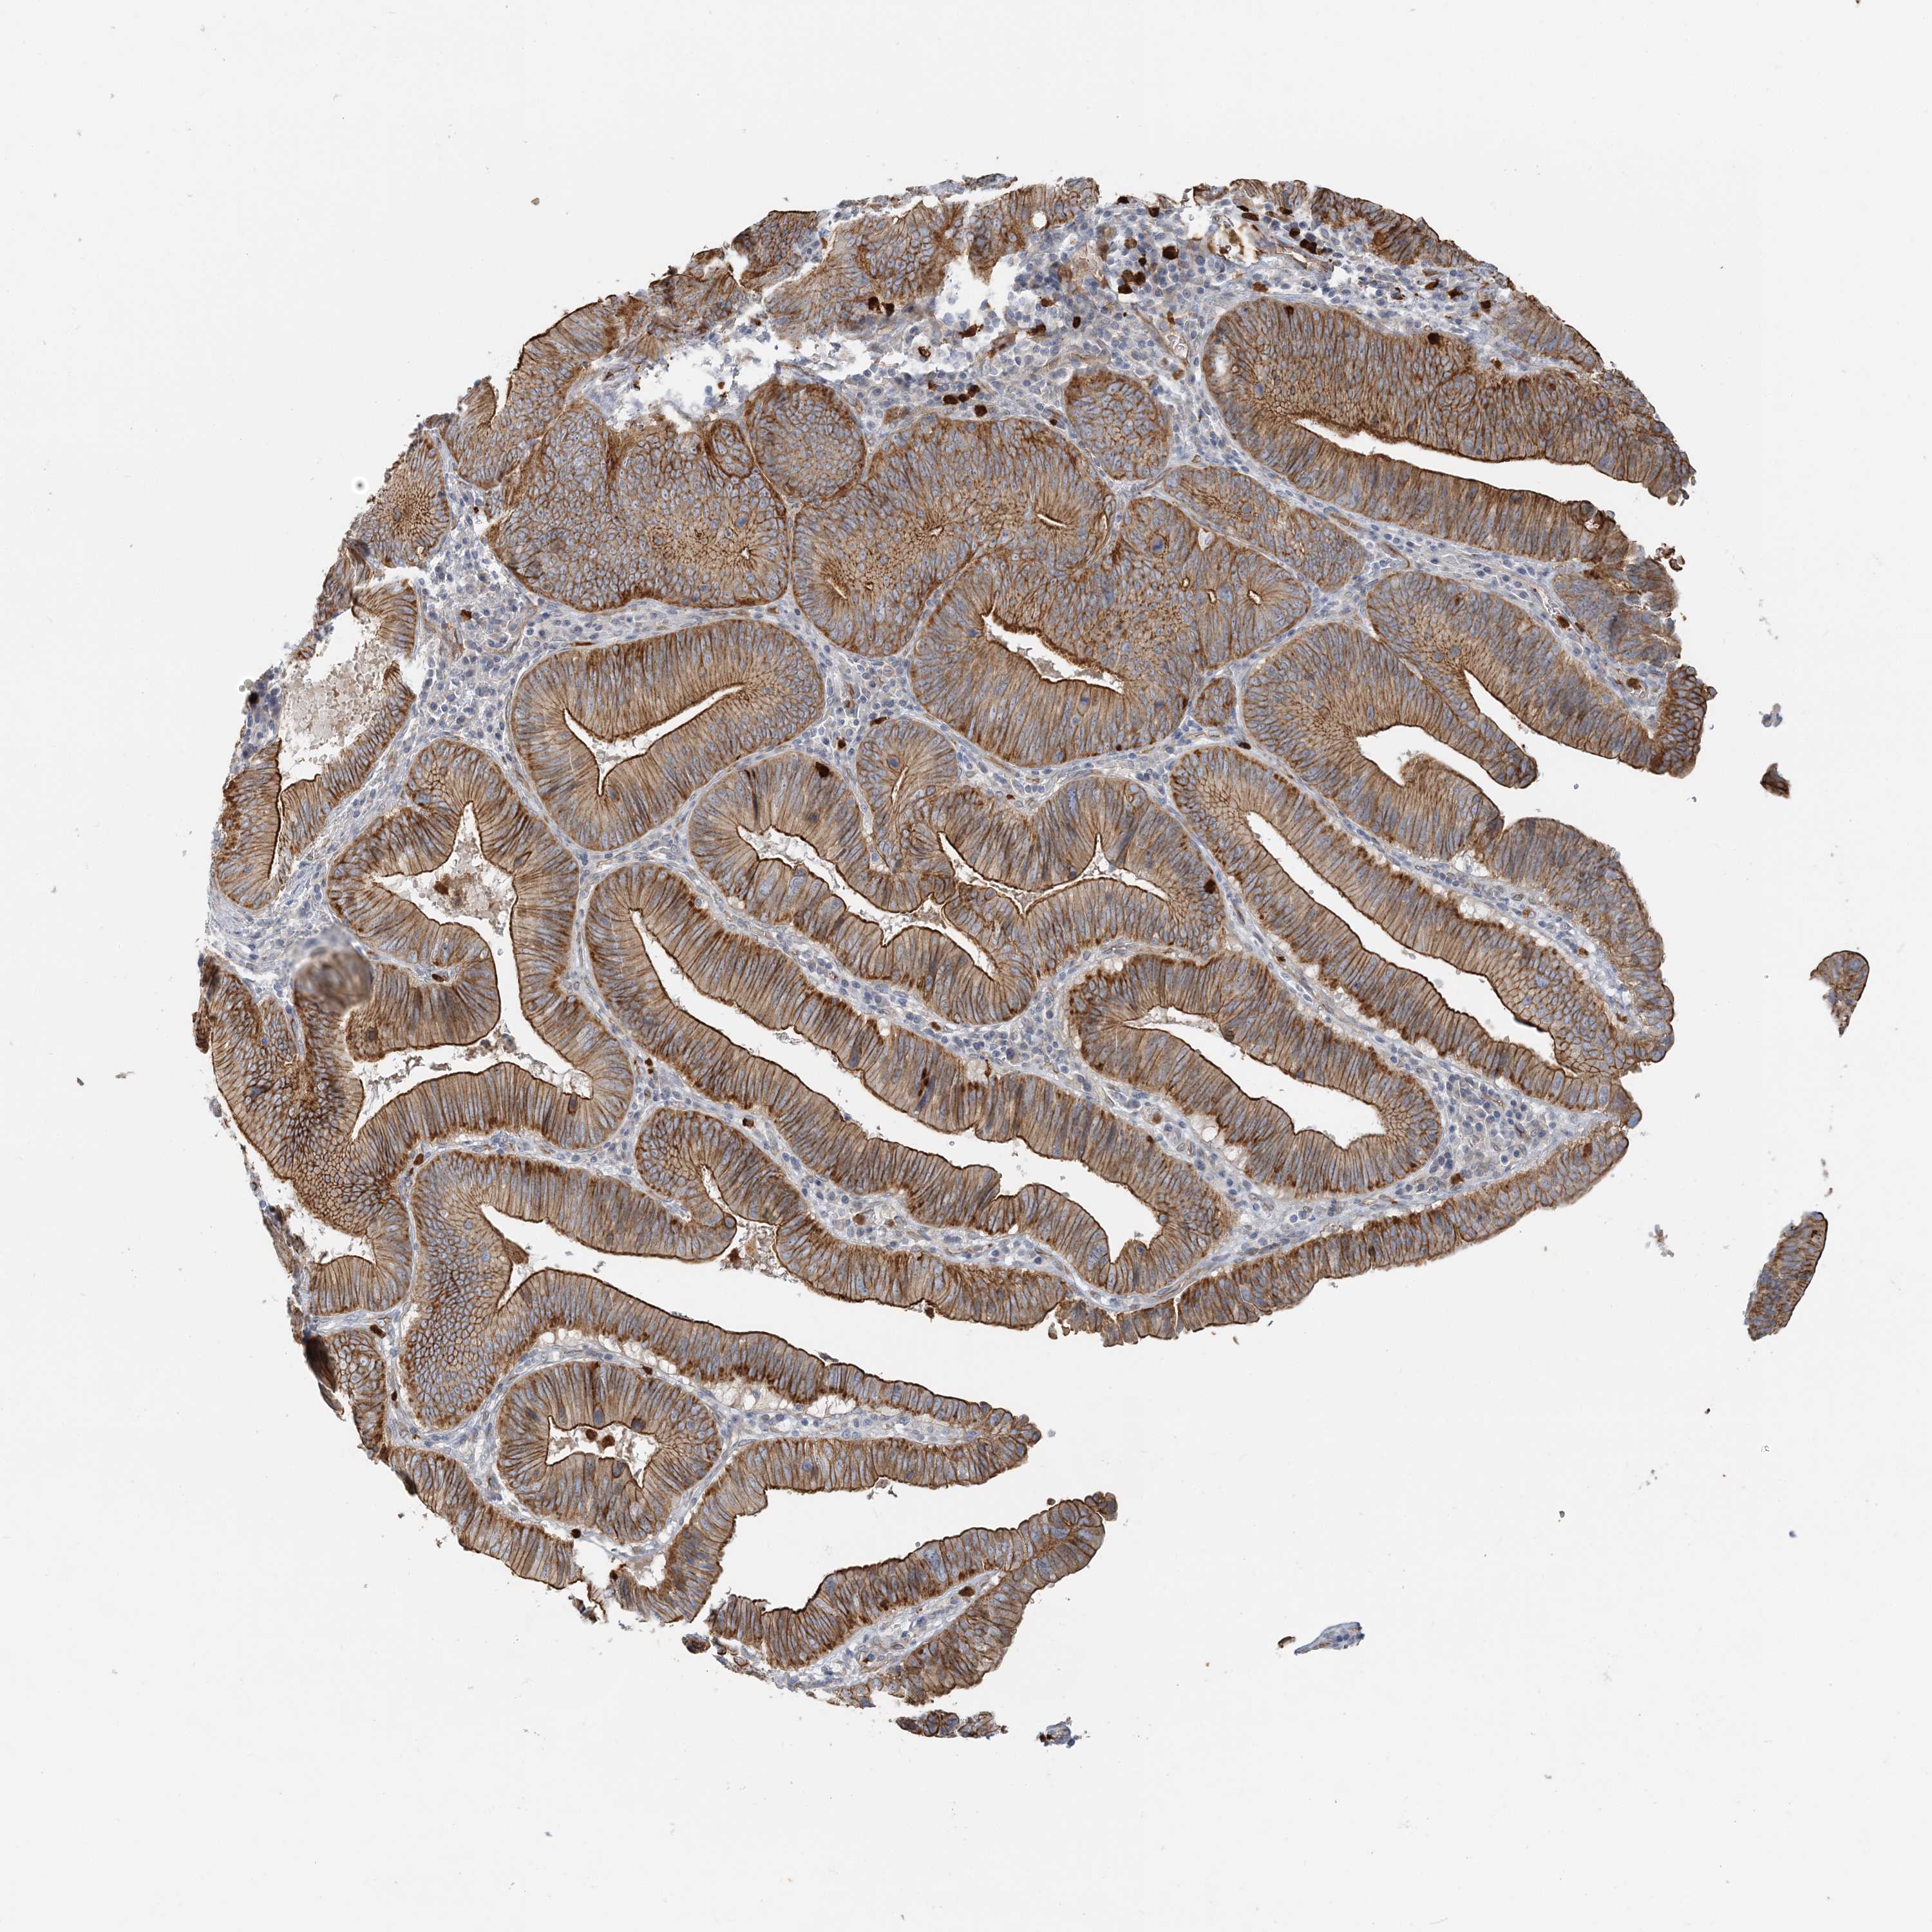

PANCREATIC CANCER - Protein expressioni

A mouse-over function shows sample information and annotation data. Click on an image to view it in a full screen mode. Samples can be filtered based on level of antibody staining by selecting one or several of the following categories: high, medium, low and not detected. The assay and annotation is described here.

Note that samples used for immunohistochemistry by the Human Protein Atlas do not correspond to samples in the TCGA dataset.

Antibody stainingi

Antibody staining in the annotated cell types in the current human tissue is reported as not detected, low, medium, or high, based on conventional immunohistochemistry profiling in selected tissues. This score is based on the combination of the staining intensity and fraction of stained cells.

Each image is clickable and will lead to virtual microscopy that enables deeper exploration of all samples and also displays staining intensity scores, fraction scores and subcellular localization as well as patient and tissue information for each sample.

Antibody HPA036805

Antibody HPA036806

Adenocarcinoma, NOS